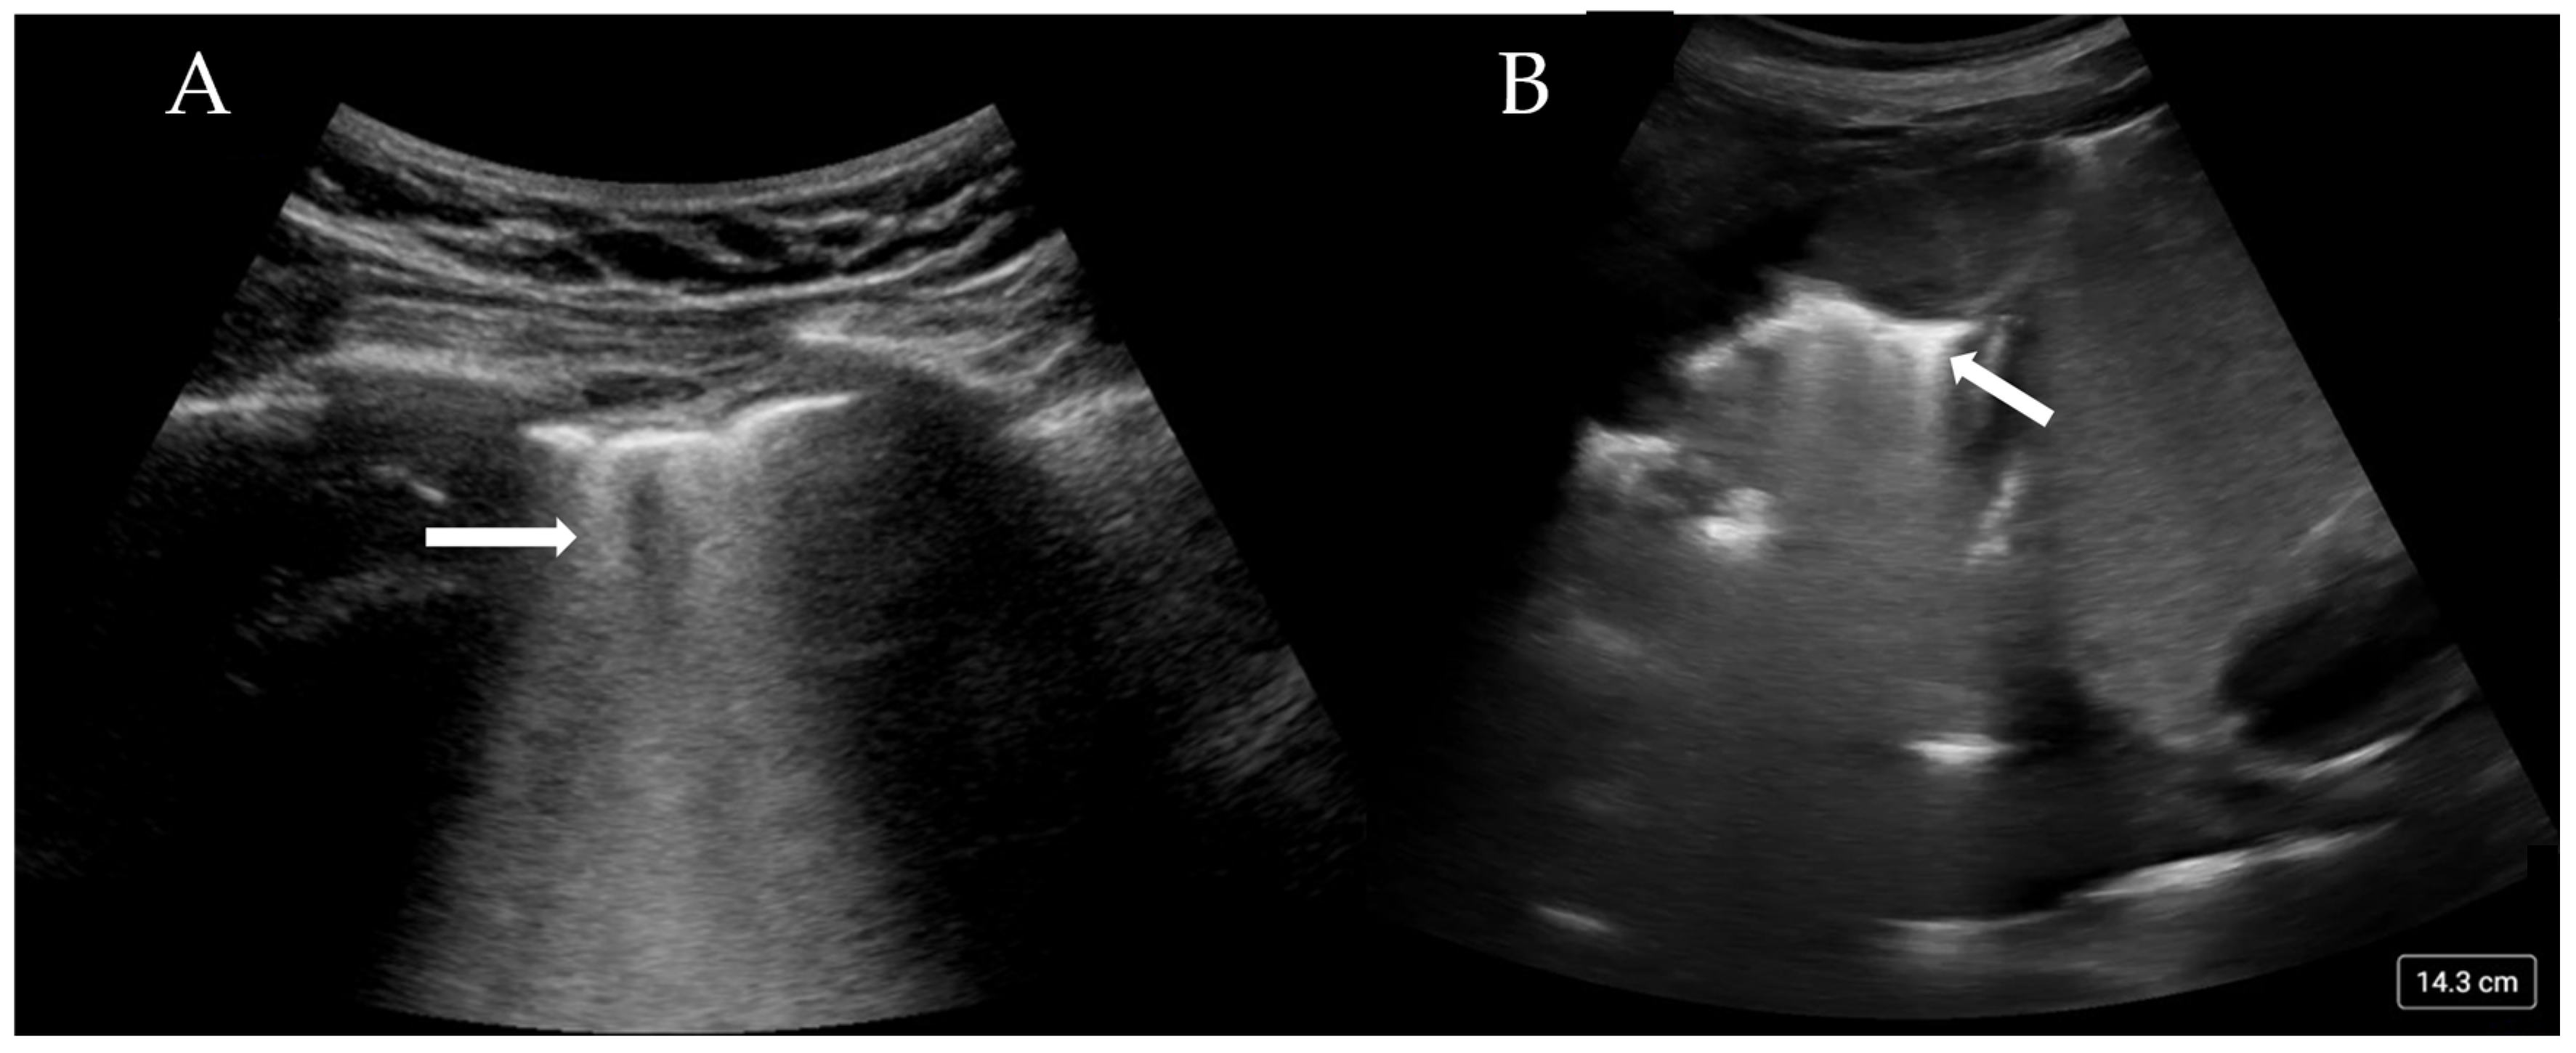

More than three B-lines are also termed ‘lung rockets’ and are considered pathological (Figure 2A). B-lines that coalesce and occupy more than 50% of the rib space are termed ’ground glass rockets’ [6]. On CT scans, B-lines often correlate with thickened intralobular septa and subpleural consolidation. The pathologies that can create B-lines are mainly divided into those that increase intralobular septal size and those that affect the pulmonary interstitial tissue. The former clinically corresponds to pulmonary oedema (whether cardiac or neurogenic), and the latter pertains to interstitial disease. The presence of B-lines has been associated with a Pulmonary Capillary Wedge Pressure (PCWP) of greater than 18 mmHg [22], although this is only the case if an intralobular disease process is occurring.

Figure 2.

(A) Confluent B-lines (arrow) consistent with pulmonary oedema and (B) consolidated and collapsed lung with shred sign (arrow).

B-lines have specific features that when combined with full LUS imaging and interpretation, can help differentiate between cardiogenic pulmonary oedema, Acute Respiratory Distress Syndrome (ARDS), interstitial pneumonia, and fibrosis (Table 1) [23].